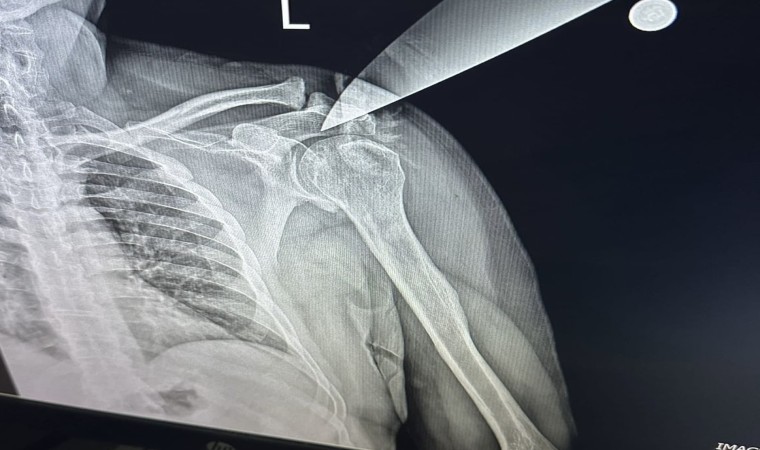

Edinilen bilgiye göre, Bursa’nın Yıldırm ilçesinde özel bir diş kliniğine 3 çocuğuyla birlikte gelen H.H.Y. (25) adlı kadın, bir süre diş doktoru Hakkı Nail Ö. ile konuştu. Yoğunluk olduğu için alamadığını ifade eden doktoru arkasını döndüğü esnada çantasında taşıdığı bıçakla saldıran kadın, bıçağı Hakkı Nail Ö.’nün omzuna saplayıp çocuklarını da bırakıp kaçtı. Korku dolu anlar yaşayan doktor ve klinikteki meslektaşları, 112 ekiplerini aradı. İhbar üzerine olay yerine gelen sağlık ekipleri, yaralı doktoru Yüksek İhtisas Eğitim ve Araştırma Hastanesine sevk ederken, doktorun omzuna saplanan bıçak ameliyatla alındı.